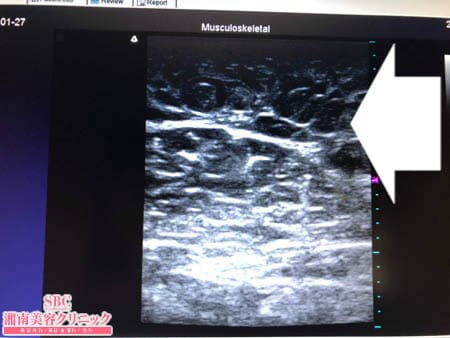

No.213080【脂肪吸引】【動画あり】湘南美容外科脂肪吸引最高責任者である竹田先生による脂肪吸引のフォトギャラリー!他院の再手術!千葉からご来院された患者様の二の腕に取り残された皮下脂肪を根こそぐ!術中3Dタッチビュー・右ちからこぶ

再手術ということもあって

癒着と硬縮が強く

脂肪吸引が非常に困難でしたが

患者様の細さに対する想いに応えるべく

徹底的に根こそぎましたので

患者様にはご満足いただけることでしょう。